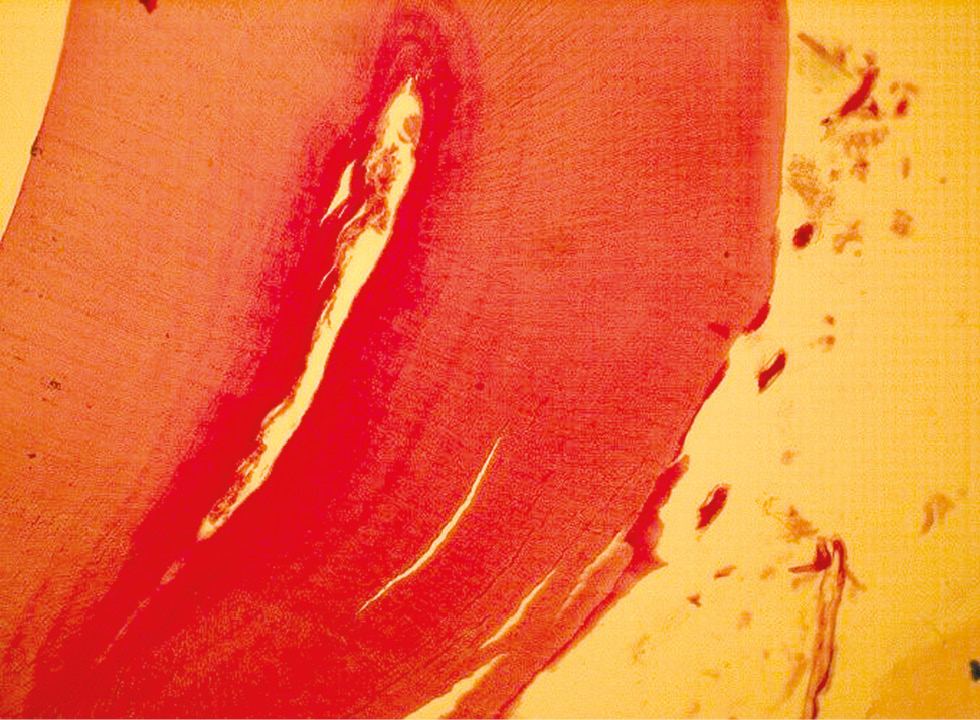

In Group 4 (3,200 mW/cm2), Day 1 findings showed preserved overall dental structure with scattered cellular infiltration of the pulp and good vascular filling (Fig. 3). Lymphocytes were noted in the loose connective tissue stroma. On Day 3, dental hard tissues remained structurally intact. Pulp microvasculature exhibited uneven blood filling, and sparse lymphocytes were present in the stroma. PAS staining revealed weak glycogen positivity in the pulp, with higher glycogen content in circumpulpal dentin compared to mantle dentin (Fig. 4). Pulp vessels remained engorged, with areas of vascular stasis.

Fig. 4. Transverse histological section of a tooth (fourth experimental group, day 1). The degree of blood filling of the dental pulp is shown. Staining according to Gabu–Dyban; ×200.